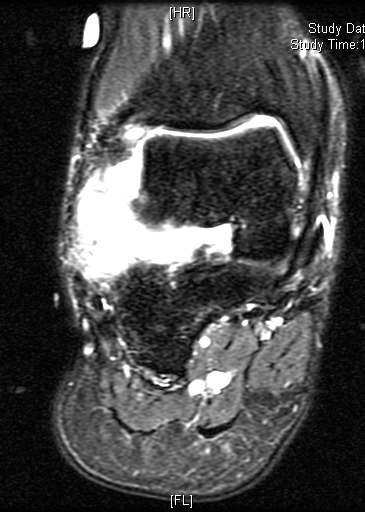

MRI

Shows multiloculated, heterogeneous mass.

“Triple Signal Intensity sign”; hypointense, isointense and hyperintense with fat on T2 – weighted MRI imaging. This sign is present in 30 to 50% of the cases. (Fig.3)

Under contrast enhancement Synovial Sarcoma appears heterogeneous and demonstrate areas of nodular enhancement.

In approximately 30% of cases a multiple vascular cannel may be identified

Synovial sarcomas may have a cystic appearance and are often mistaken for ganglion cysts especially those adjacent to tendons and in the foot and ankle.